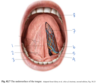

Which muscle is labeled by #1?

What is its action?

Aryepiglottic muscle

Pulls the epiglottis posteriorly to help close the larynx - opposes the thyroepiglottic muscle

(Restricts the opening like a purse string, but doesn’t close it completely)

Which muscle is labeled by #2?

What is its function?

Genioglossus

-

Protrude the tonuge

- The only muscle that protrudes the tongue!

- Deviate the tongue to the opposite side

- Depress the tongue

Which structure is labeled by #3?

Geniohyoid

What structures serve as the posterior boundary of the oral cavity?

Sulcus terminalis (#4)

Palatoglossal arches (#5)

Which structure is labeled by #4?

Levator palati

Which structure is labeled by #8?

Apex of the tongue

Which structure is labeled by #3?

Styloglossus muscle

Which muscle is labeled by #3?

What is its function?

Hyoglossus

Retract the tongue

Which structures are labeled by #6?

Deep lingual artery and vein

Which fold is labeled by #2?

Vestibular fold (aka false vocal fold)